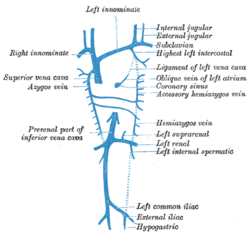

Diagram showing completion of development of the parietal veins.

Diagram showing completion of development of the parietal veins.- Pelvic contents: male.Superior view.Deep dissection.